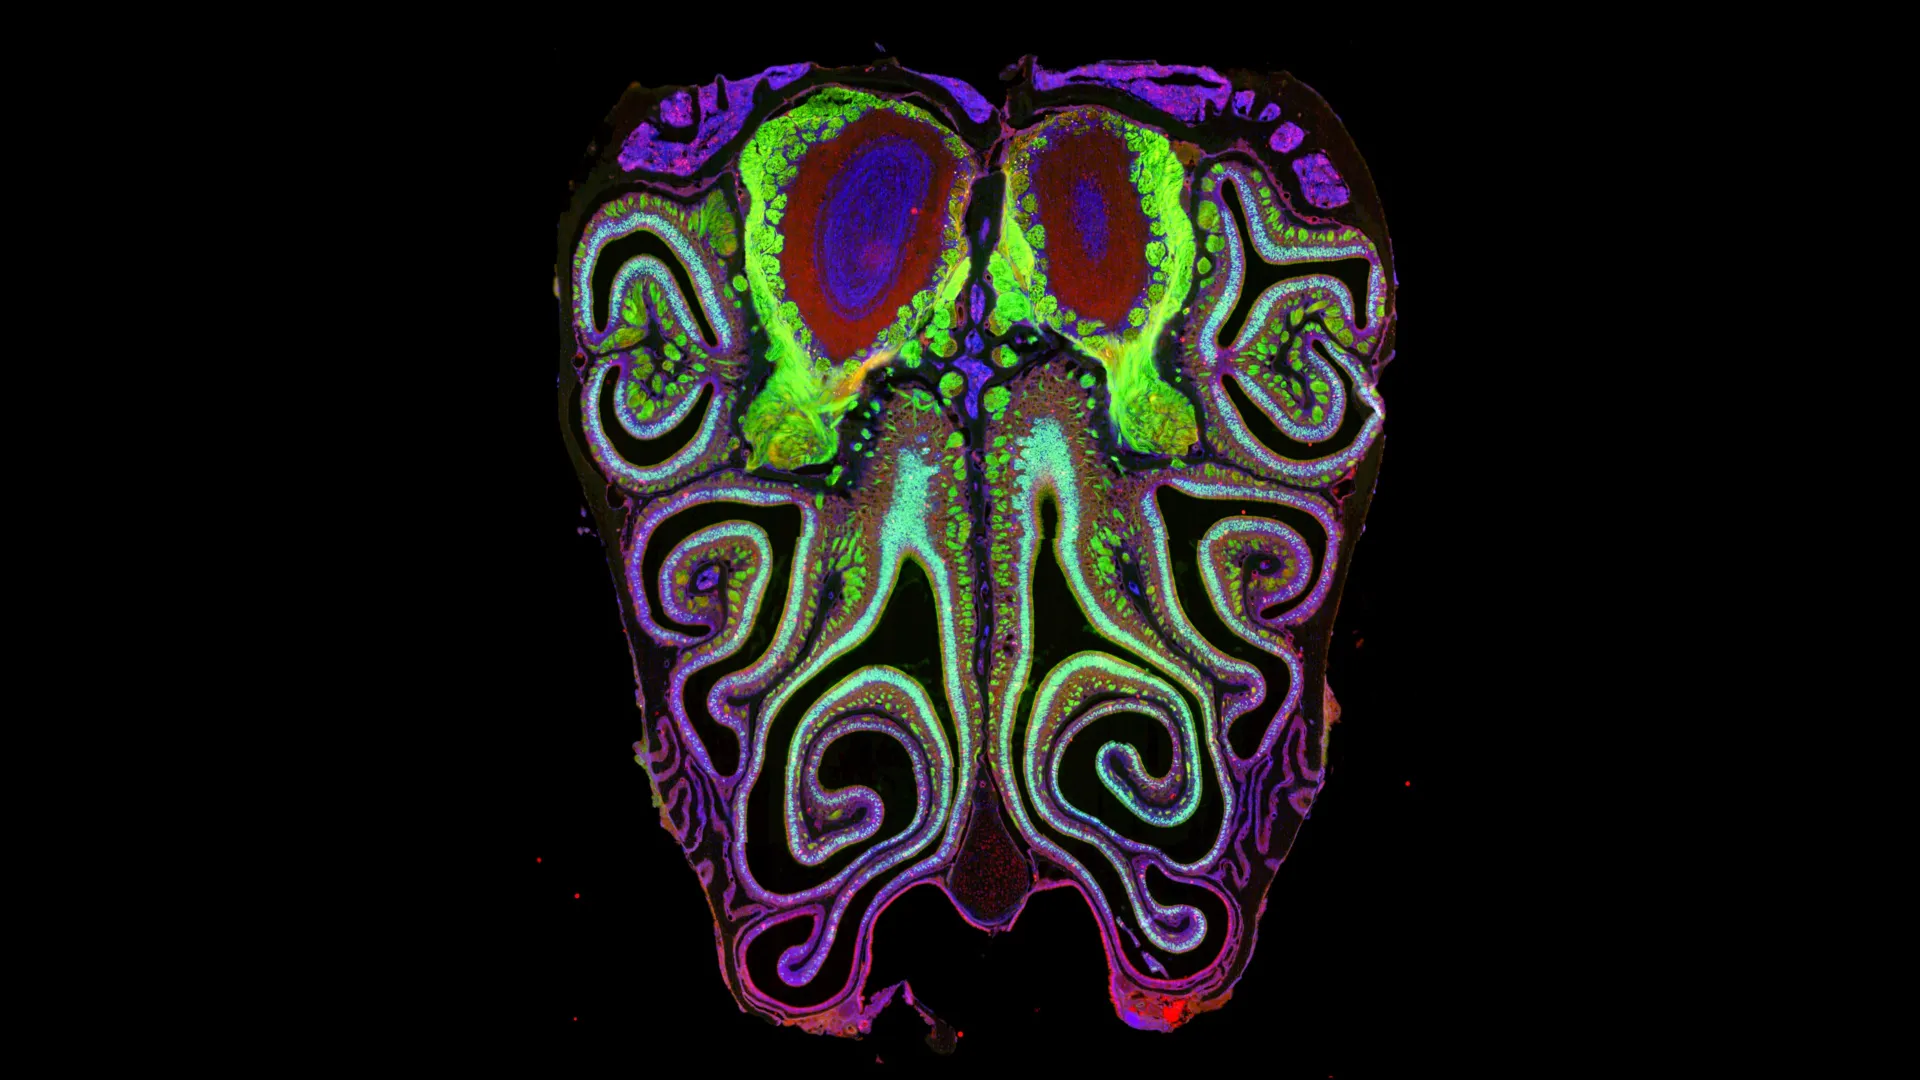

A pesquisa liderada por Sandeep Datta e sua equipe resultou na criação do primeiro mapa detalhado que mostra como mais de mil tipos de receptores olfativos estão organizados no nariz dos ratos. Ao contrário do que se pensava, esses neurônios formam bandas horizontais, agrupadas por tipo de receptor, em vez de estarem dispostos de maneira aleatória. Essa nova organização traz uma nova perspectiva sobre o funcionamento do sistema olfativo, conforme relatado no estudo publicado em Cell.

Os cientistas analisaram aproximadamente 5,5 milhões de neurônios em mais de 300 ratos, utilizando técnicas avançadas como sequenciamento de célula única e transcriptômica espacial. Essa abordagem permitiu identificar não apenas quais receptores cada neurônio expressa, mas também sua localização exata. O resultado foi um padrão claro e consistente de organização, que se repetiu em todos os animais estudados, refletindo a maneira como as informações olfativas são mapeadas no cérebro.

A nova organização dos receptores olfativos pode transformar a compreensão científica sobre o olfato. O estudo sugere que a estrutura organizada dos receptores no nariz se alinha com os mapas correspondentes no bulbo olfatório do cérebro, indicando um sistema coordenado para a transmissão de informações olfativas. Essa descoberta pode abrir caminhos para novas pesquisas sobre como os sentidos são processados e como podem ser restaurados em casos de perda olfativa.